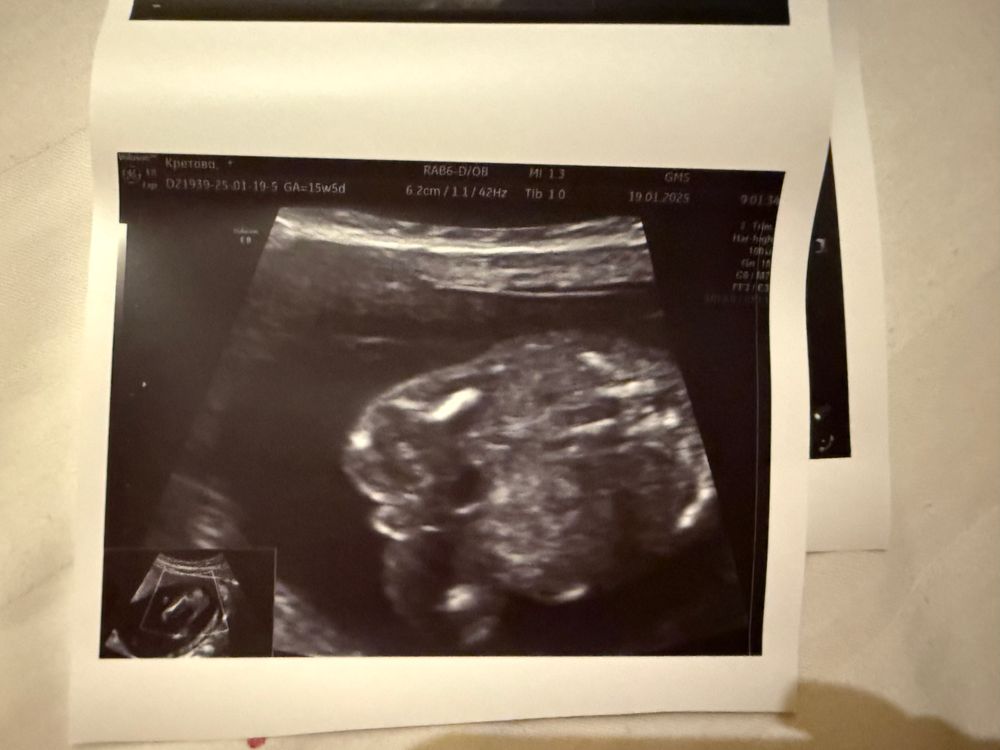

С первого скринга жаркие споры по поводу пола нашего малыша 😁 Сегодня 15 недель 5 дней, но по размеру плода мне ставят 15 и 2. На ранних сроках чуть позже увидели эмбрион (я еще испугалась, что его нет в пя), в итоге сказали, что вероятнее всего, была поздняя овуляция.

сегодгя было сложно что-то рассмотреть, с нетерпением жду 2 скрининга, но мне очень уж интересно, какого пола наше сокровище. Посмотрите на фотку и сделайте свои предположения, пожалуйста ☺️ Как я понимаю, это вид спереди😁

Eva , вот я попробовала скрин сделать, там как будто в определенный момент между ножек беленькая палочка была, я думала, что это м. А вот на сегодняшней фотке не совсем гладко, но и нет выраженной ясности)

Юлия Флинк, к сожалению на фотках с 1 скрининга не разберешь, а вот если на фотках вашего последнего узи вид между ножек( скорее всего да), то похоже на мальчика

19.01.2025